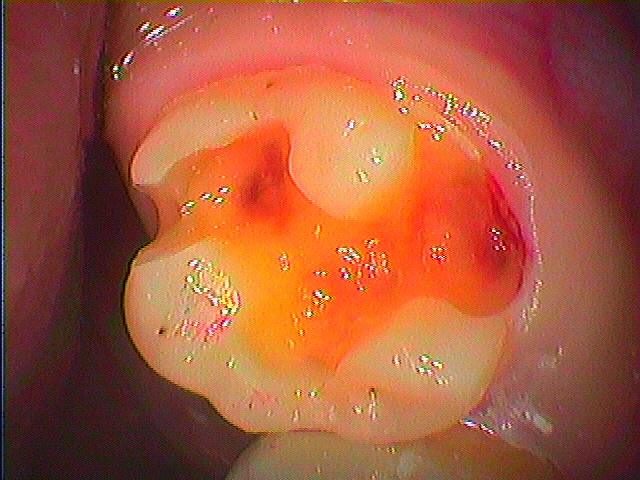

右上6番の銀歯をはずして虫歯治療 セラミックによる審美治療|お知らせ |広島市安佐南区の歯科医院 右上6番の銀歯をはずして虫歯治療 セラミックによる審美治療 トップ お知らせ・ブログ お知らせ 右上6番の銀歯をはずして虫歯治療 セラミックによる審美治療 右上6番の銀歯をはずして虫歯治療 セラミックによる審美治療 この銀歯をはずしていきます 下はこのように虫歯になっていました 横も大きく虫歯になっていました このように大きく虫歯です CR樹脂にて覆罩を行っています セレックセラミックが綺麗に入りました Web診療予約 初めての方へ 選ばれ続ける理由 院内設備について 歯が痛いしみる一般歯科 歯がぐらぐらする歯周病 健康な歯を保ちたい予防歯科 子供の虫歯予防をしたい小児歯科 銀歯をセラミックに審美歯科 白い歯を目指しませんか?ホワイトニング 矯正専門医がいるので安心矯正歯科 抜けた歯を補いたいインプラント・入れ歯 医院案内 スタッフ紹介 メリィハウス歯科クリニックオフィシャルホームページ ラベンダー歯科クリニックオフィシャルホームページ お知らせ・ブログ ホーム 診療科目 一般歯科 歯周病治療 予防治療 小児歯科 審美治療 ホワイトニング 矯正歯科 入れ歯・インプラント マウスピース矯正 初めての方へ 院長・スタッフ 設備紹介 医院案内・アクセス メニューを閉じる